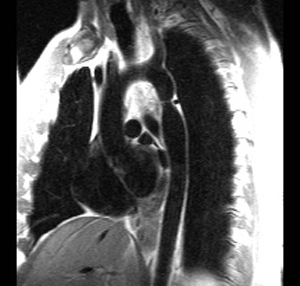

7) This spin echo image shows what aortic abnormality?